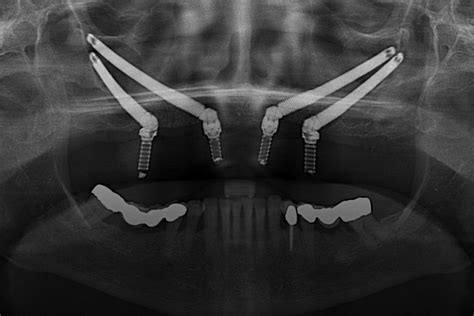

| Implantes dentales | 799 € | Son una alternativa a las prótesis dentales para sustituir las piezas dentales perdidas. Los precios varían en función del número de implantes necesarios y de la técnica utilizada. |

- Implantes Cigomáticos: Este tipo de implantes se colocan en el maxilar superior, donde el hueso es más fino.